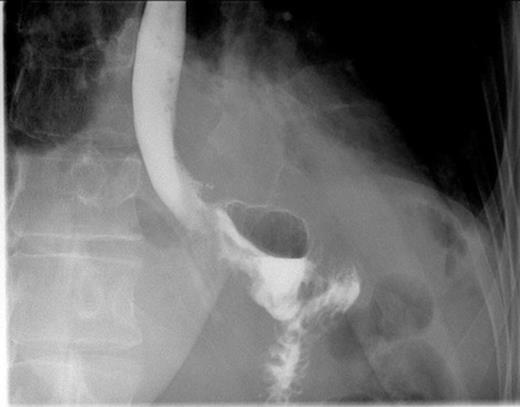

Postoperative contrast swallow

The whole stomach wall was submitted for histological microscopic examination in 67 blocks. No evidence of dysplasia or early foci of signet ring cell carcinoma were seen. The resected lymph nodes were unremarkable. The patient’s postoperative course was uncomplicated with return of bowel function on day 6 and discharge home on day 11. A postoperative contrast swallow was normal on postoperative day 3 (Figure 1). She remains well 5 months following surgery, with satisfactory wound healing (Figure 2).